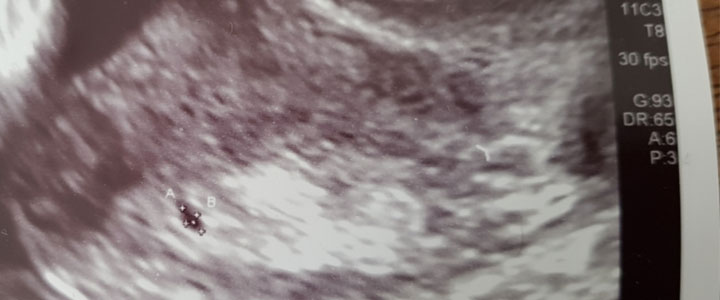

Zwanger, maar hoeveel weken gevorderd op de eerste echo?

Plots wat bloedverlies, niet weer een miskraam… Volgens de calculatie zou ik uitgerekend zijn op 27 januari 2019 en nu dus 7 weken en 1 dag zwanger zijn. Maar gezien mijn wisselende cyclus zou het ook korter ...